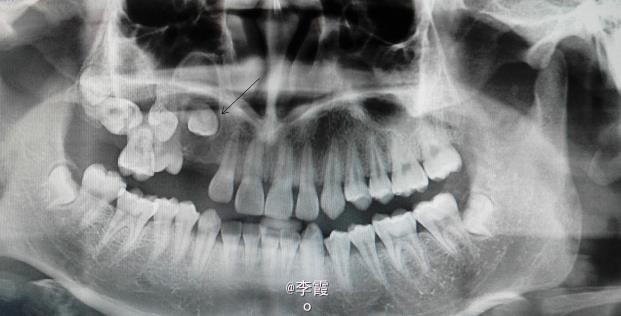

患者、陆xx、男、17岁。主诉:右侧上后牙未萌出,要求治疗。平素体质一般,无药物、食物过敏史,无高血压、心脏病等系统性疾病。

口腔专科检查:13、14和17未萌出。15 牙齿90°扭转萌出,左侧上颌牙齿均正常萌出。x线 全景片:13牙冠周围有约红枣大小牙囊影。14高位阻生、17水平阻生。

诊断:(1)13含牙囊肿(2)14高位垂直阻生。(3)17高位水平阻生。处理:(1)建议手术拔除15及去除13牙冠周围牙囊,保留13。(2)半年后做13和15正畸牵引。17暂时不做处理。